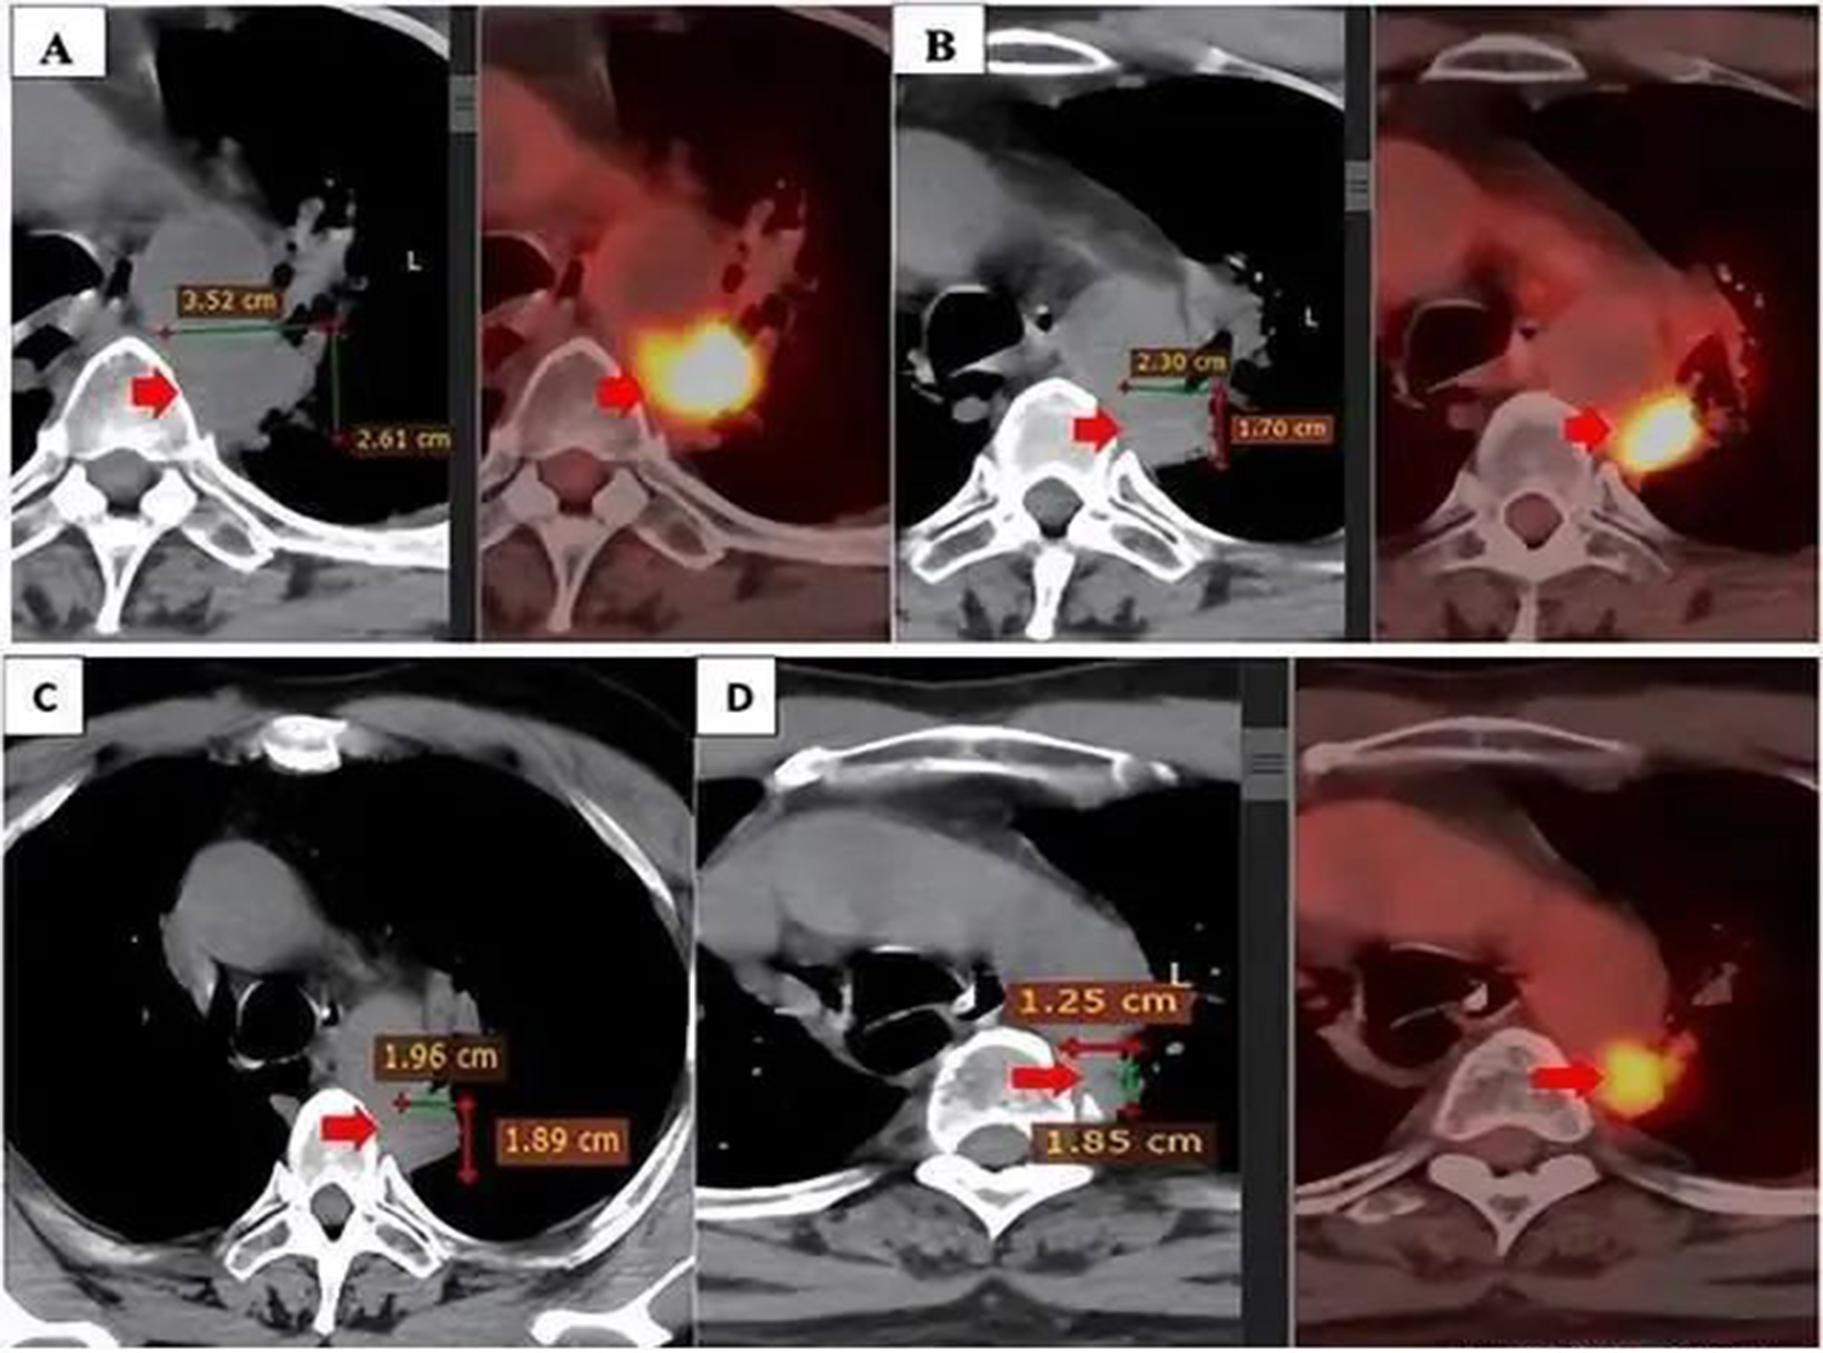

从2019年6月到2019年12月,患者接受了第三周期的3个周期的卡铂650mg(AUC5)加紫杉醇300mg(175mg/m2)联合放疗的一线治疗。症状获得了部分缓解,临床症状和副临床症状都有所改善。患者的正电子发射断层扫描(PET)/CT扫描显示原发肿瘤的大小减小(12×7mm),肿瘤标志物值于2019年12月恢复正常。

尽管如此,该疾病在2020年5月继续发展。PET/CT扫描显示原发性肿瘤大小为28×29mm,标准化摄取值(SUVmax)11.2,与纵隔胸膜和主动脉粘连。此外,左侧锁骨上淋巴结的大小为9×6mm,左侧门中的一些小淋巴结的尺寸小于10mm。PD-L1表达阳性(25%),接受4个周期的阿利姆塔(500mgx2)、卡铂(150mgx2,450 mgx1)、可瑞达(4mlx2)的二线治疗。然而,他的病情在2020年6月的 PET/CT 扫描中表现不稳定。由于疾病进展,患者的治疗方案发生了变化。

2021年3月和2021年9月进行的PET/CT扫描显示,与联合治疗前相比,原发肿瘤的大小显著减少。此外,没有发现两侧的纵隔淋巴结和锁骨上淋巴结。